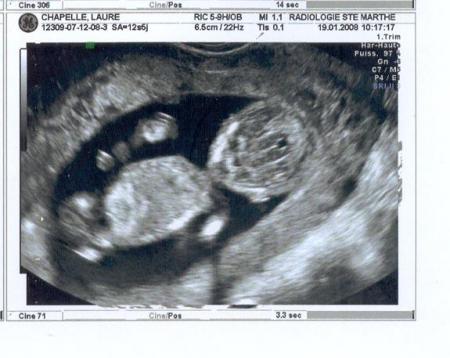

échographie du 1er trimestre.

27/11/2008 19:54 par lauremanulucas

le 19 janvier 2008, c'est la rencontre officielle où ils me découvrent enfin! grande émotion... j'ai quand même pas mal changé! 170 battements par minute, je suis plus nerveux et ça ne fait que commencer!